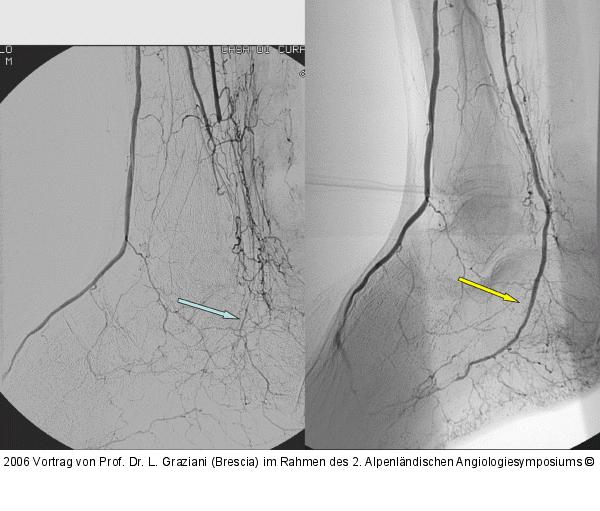

Vortrag von Prof. Dr. L. Graziani (Brescia) im Rahmen des 2. Alpenländischen Angiologiesymposiums

PTA of the foot arteries in diabetics: Extremities Extreme Angioplasty

Abbildung 21: Revaskularisation